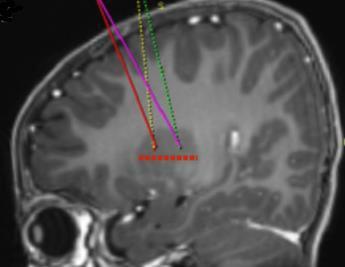

- i siti target di infusione sono definiti secondo lo standard della pratica neurochirurgica stereotassica. Upstaza viene somministrato come infusione bilaterale (2 infusioni per putamen) mediante una cannula intracranica. I 4 target finali per ciascuna traiettoria devono essere definiti come 2 mm dorsale verso (sopra) i punti di destinazione anteriore e posteriore nel piano medio-orizzontale (Figura 1).

Figura 1I quattro punti target per i siti di infusione